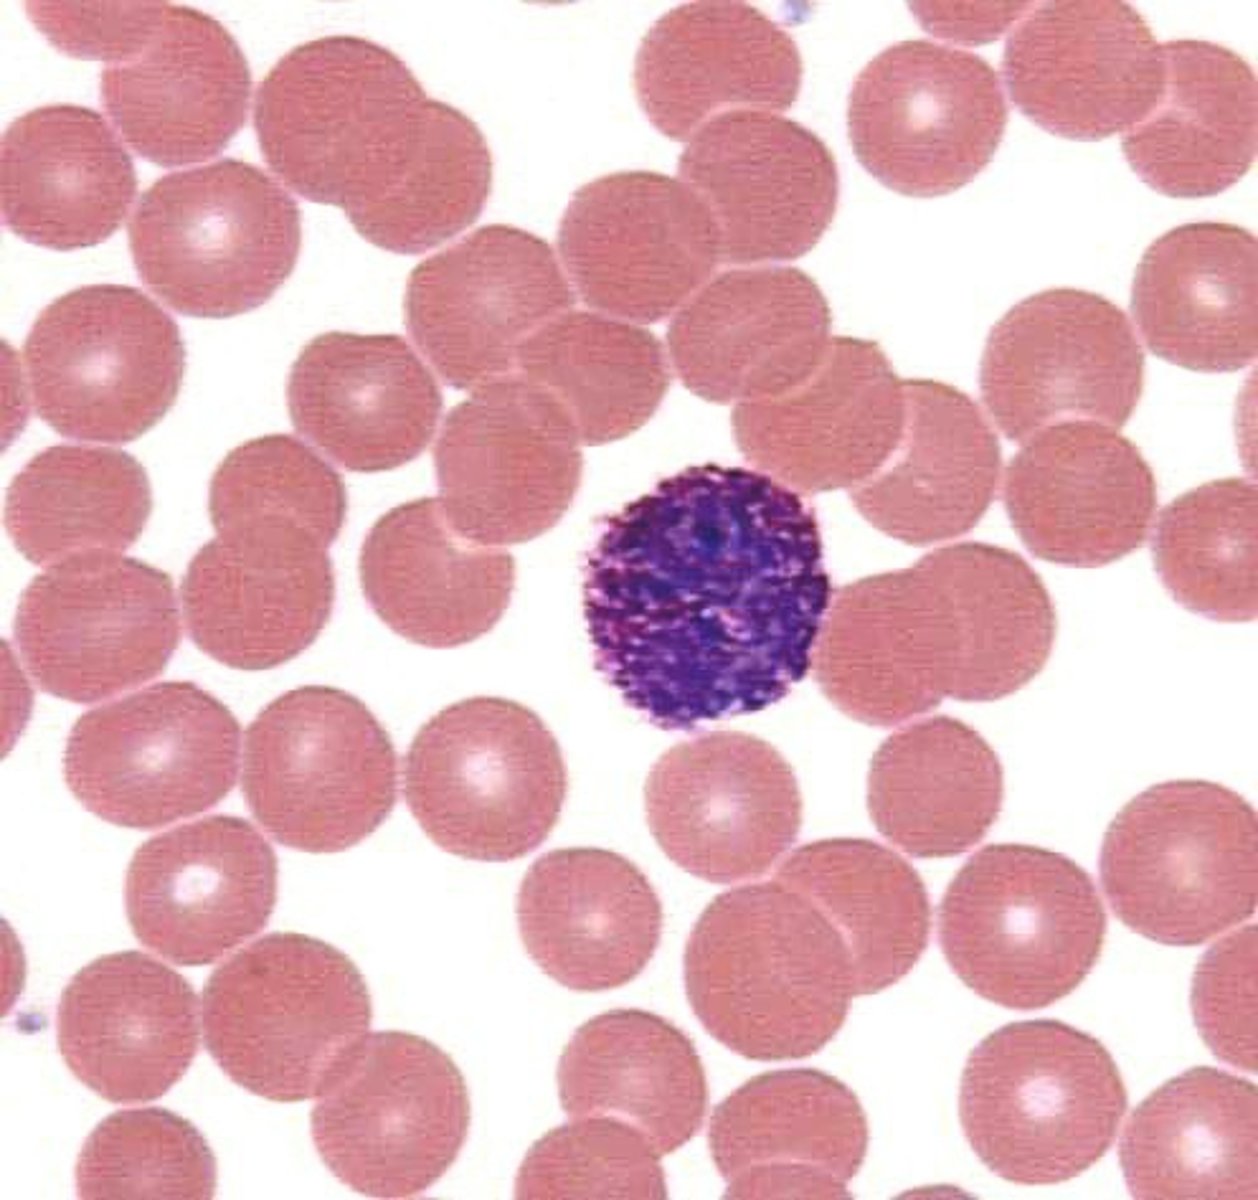

Blood

What is this?

Abnormal

Is this blood slide normal or abnormal?

Neutrophil

what is this?

lymphocyte

what is this?

Macrophage

what is this?

Eosinophil

what is this?

monocyte

what is this?

basophil

what is this?

platelet

what is this?

Red Blood Cell

what is this?